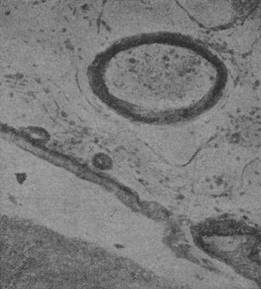

Увеличение волокнистой соединительной ткани наблюдается также вокруг кровеносных сосудов, но более важны изменения самих стенок сосуда и в особенности процессы, происходящие в периваскулярных пространствах и вообще в их окружности. Что касается самих сосудов, то здесь прежде всего можно встретить гиалиноз прекапиляров; но на него нужно смотреть все-таки как на осложнение; менаду тем очень постоянны изменения, имеющие прямое отношение к существу болезни. Здесь прежде всего нужно иметь в виду набухание и разрастание элементов эндотелия мелких сосудов, ведущее к более или менее значительному ограничению просвета (рис. 90).

Рис. 90. Разрастание элементов сосудистой стенки при врожденном сифилисе.